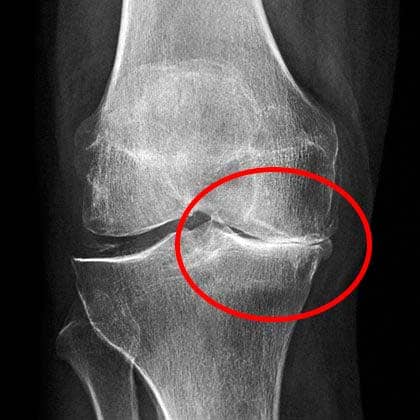

Izgled mog koljena u tom trenutku: jaka, nepodnošljiva bol.

Nakon pregleda, liječnica je dugo gledala rendgenske snimke i rekla mi da prestanem s bilo kakvim teškim fizičkim radom. Rekla mi je da ne podižem ništa teže od 2 kg.

Rendgenske snimke pokazale su velik problem u koljenu.

Naravno, to za mene nije dolazilo u obzir! Kako da radim svoj posao ako ne smijem ništa dići? Ja volim taj posao, unatoč svim njegovim nedostacima. Odlučila sam potražiti drugo mišljenje. Ali ono me još više prestrašilo! Bez konkretne dijagnoze, liječnik me jednostavno obavijestio da ću bez operacije koljena uskoro biti nesposobna za rad. Operacija bi me koštala 35.000 eura! Nisam imala toliko novca i pokušala sam dogovoriti operaciju tek za šest mjeseci, nadajući se da ću do tada uspjeti sve skupiti.

Ovako danas izgleda moje zdravo koljeno.